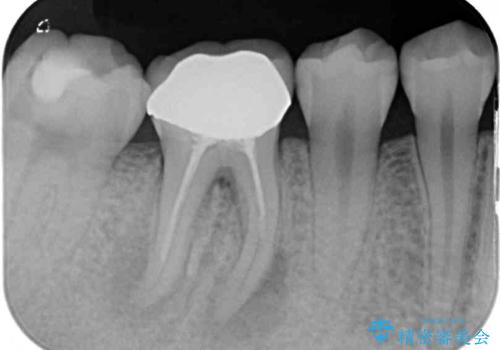

- 奥歯の歯肉から定期的に膿が出てくるとのことで来院された患者様です。

レントゲン写真などの診察を行った結果、根管治療が必要であったため、現在のクラウンを除去し、根管治療を行うこととしました。

根管治療後は症状を確認し、速やかにオールセラミッククラウンにて補綴治療を行うこととしました。